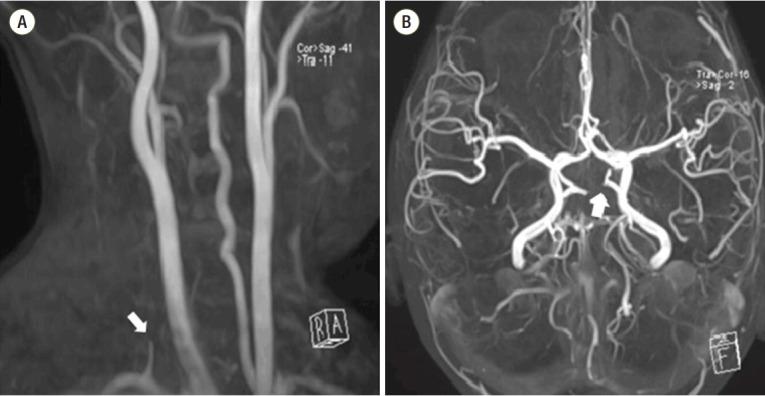

Acute cerebral infarctions are rare in children, however they can occur as a complication of a (MP) infection due to direct invasion, vasculitis, or a hypercoagulable state. We report on the case of a 5-year-old boy who had an extensive stroke in multiple cerebrovascular territories 10 days after the diagnosis of MP infection. Based on the suspicion that the cerebral infarction was associated with a macrolide-resistant MP infection, the patient was treated with levofloxacin, methyl-prednisolone, intravenous immunoglobulin, and enoxaparin. Despite this medical management, cerebral vascular narrowing progressed and a decompressive craniectomy became necessary for the patient's survival. According to laboratory tests, brain magnetic resonance imaging, and clinical manifestations, the cerebral infarction in this case appeared to be due to the combined effects of hypercoagulability and cytokine-induced vascular inflammation.

急性脑梗死在儿童中较为罕见,然而,它可能作为支原体(MP)感染的并发症出现,原因包括直接侵袭、血管炎或高凝状态。我们报告了一例5岁男孩的病例,该男孩在诊断为MP感染10天后,在多个脑血管区域发生了广泛的中风。基于脑梗死与大环内酯耐药MP感染相关的怀疑,该患者接受了左氧氟沙星、甲泼尼龙、静脉注射免疫球蛋白和依诺肝素治疗。尽管采取了这种治疗措施,脑血管狭窄仍在进展,为了患者存活,进行减压颅骨切除术成为必要。根据实验室检查、脑磁共振成像和临床表现,该病例中的脑梗死似乎是由于高凝状态和细胞因子诱导的血管炎症的联合作用所致。